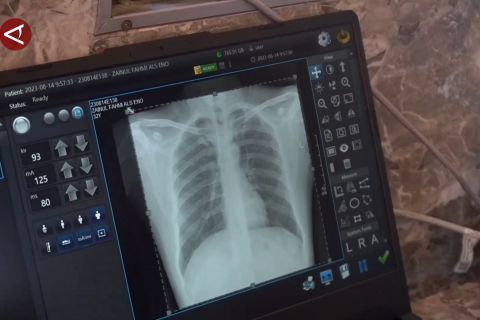

ANTARA - Sebagai langkah untuk deteksi dini penyakit Tuberkulosis (TBC), Dinas Kesehatan Kota Padang, Sumatera Barat mulai melakukan tes skrining TB ke puskesmas, dengan menggunakan mobile X Ray . Tes skrining TB yang digelar di Puskesmas Koto Panjang Ikua Koto, Kecamatan Koto Tangah pada Sabtu, (22/02) menyasar sekitar 150 orang, dengan kriteria pasien diabetes melitus, pasien perokok aktif, pasien yang punya kontak erat dengan pasien TB, pasien malnutrisi dan penderita HIV/AIDS. (Melani Friati/Dudy Yanuwardhana/Nabila Anisya Charisty)